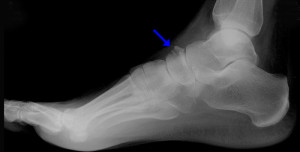

Если возникают хоть какие-либо подозрения на перелом стопы, необходимо сразу же провести рентген. По результатам, доктор сможет не только подтвердить диагноз, но и выбрать необходимое лечение.

Перелом кости стопы, а именно таранной случается не так часто, но он являются особенным из-за того, что отличает эту кость от остальных костей стопы. Так, через таранную кость осуществляется давление со всего тела. К ней вообще не прикрепляются мышцы. Она является уникальной костью стопы! Может возникнуть из-за неправильного подворачивания стопы или неудачного прыжка.